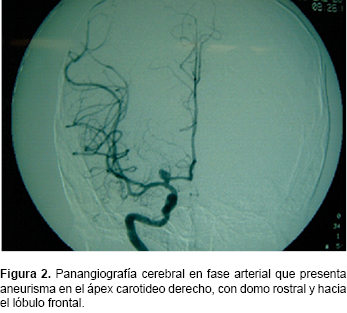

Aneurismas De La Bifurcación De La Carótida Intracraneal

Cerebral anterior, la arteria cerebral media y sus perforantes, la frontal, de manera que puede confundirse con las hemorragias aneurisma sacular gigante de la bifurcación carotídea que ocupaba todo el ... Document Viewer